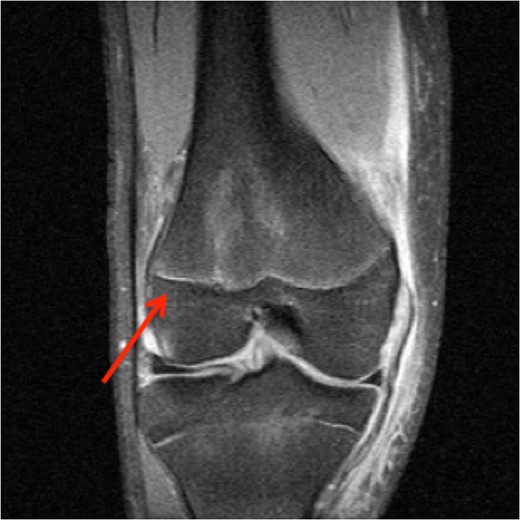

A 16-year-old elite level footballer presented to our clinic with persistent symptoms of instability following a knee injury. The patient had sustained a valgus force to his knee during a tackle. He had been treated by his football club's doctor after an magnetic resonance imaging (MRI) scan had demonstrated a MCL injury (Fig. 1).

The patient's initial management was non-operative with a period of knee protection with a range of movement brace and intensive rehabilitation. Approximately 3 months after the index injury he returned to competitive football but shortly after his return sustained a further valgus injury and despite further conservative treatment was unable to return to sport. He was referred to our service with ongoing instability symptoms. Upon clinical assessment we noted an asymmetric valgus alignment of the knee and abnormal laxity of the MCL. Radiographic investigations revealed an abnormality of the lateral distal femur and alignment radiographs confirmed the valgus mal-alignment with abnormal opening of the medial tibio-femoral joint space on single-leg stance radiographs (Figs 2–4). We obtained the patient's MRI scan and reviewing this with Radiology colleagues revealed subtle changes of increased lateral femoral physis fluid density on T-2 weighted images consistent with a Salter Harris Type V injury (Fig. 5).

MRI showing increased fluid density around the lateral distal femoral physis (red arrow).